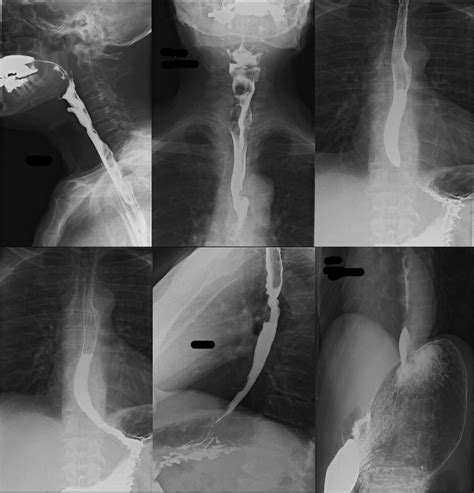

When a patient presents with dysphagia (difficulty swallowing), the Achalasia Barium Swallow serves as a cornerstone diagnostic test. During this procedure, the patient drinks a liquid containing barium, a contrast material that coats the inner lining of the esophagus. As the patient swallows, a radiologist uses fluoroscopy—a continuous X-ray beam—to observe the movement of the liquid down the esophagus in real-time.

The hallmark finding on a barium swallow study for achalasia is the "bird’s beak" appearance. This occurs because the LES remains tightly closed, causing the esophagus above it to dilate and taper to a narrow point, resembling the beak of a bird. This visual evidence is often the first major indicator that confirms a diagnosis of achalasia.

While the barium swallow is excellent for identifying the structural narrowing and the “bird’s beak” sign, it is often used in conjunction with other tests to confirm the diagnosis and assess the severity of the condition. The following table illustrates how different tests compare in the workup for esophageal motility disorders.

Achalasia Barium Swallow Structural/Functional observation High; identifies "bird's beak" and esophageal dilation.